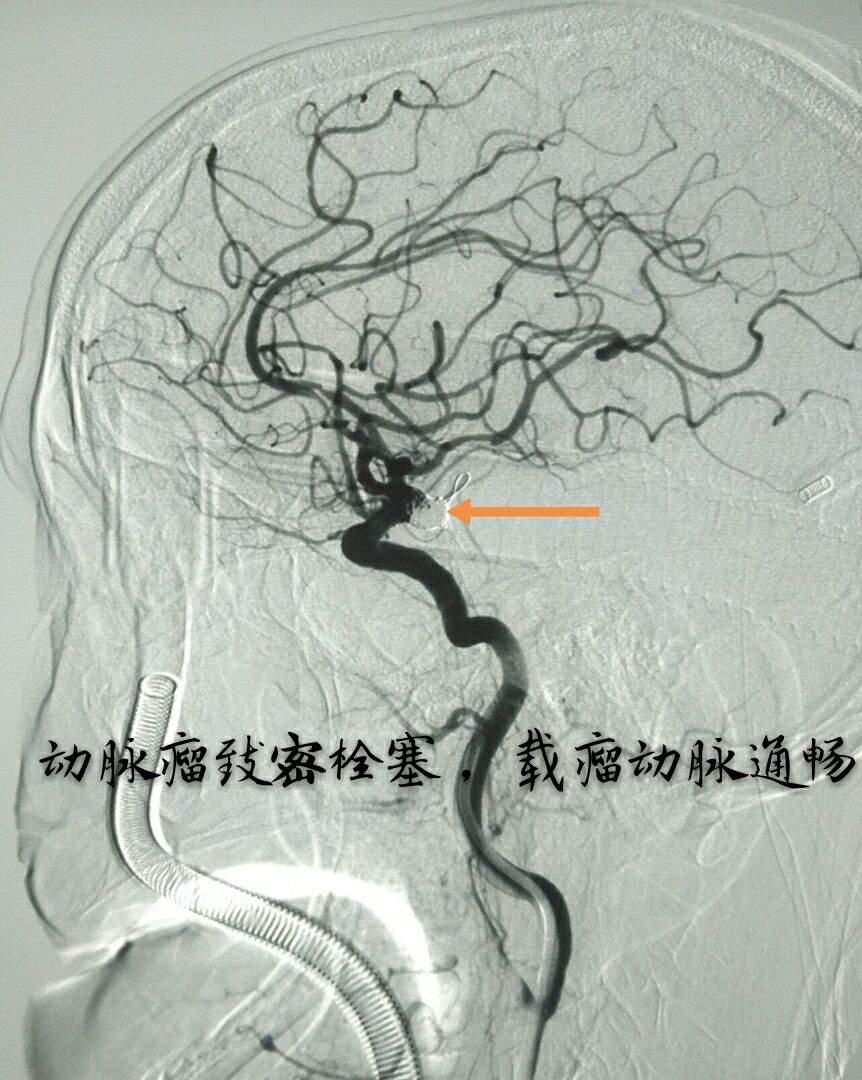

病例四:80岁男性患者,主症:头痛、脑鸣2年,DSA示左侧大脑中动脉下干大动脉瘤,绝对宽颈,载瘤动脉累及程度重

最准致密栓塞动脉瘤,载瘤动脉完美塑型并受到保护,难点:瘤颈极宽,辅助支架导管通过动脉瘤到达远端困难,最准微导管塑型成大弯,微导丝成袢通过动脉瘤到达远端,成功释放支架,动脉瘤栓塞后患者头痛、脑鸣症状消失